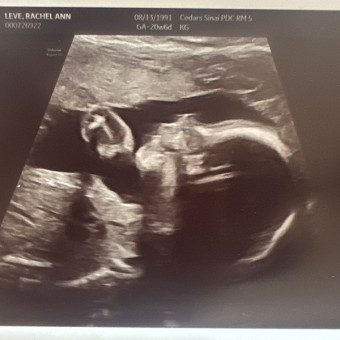

Rob Garsson & Rachel Leve's Baby Registry

Rob Garsson & Rachel Leve

Los Angeles, CA

December 6, 2025